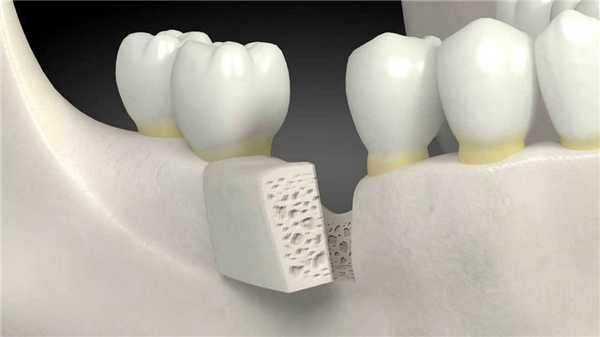

Большая часть скелета состоит из костного матрикса. Это твердый материал, который придает скелету прочность. Внутри находятся живые костные клетки, которые создают и поддерживают структуру матрикса. Эти клетки «подчиняются» особым белкам — факторам роста, используемым для регенерации костей.

Здесь на помощь хирургам приходят костные материалы.

Костные трансплантаты (графты) могут служить основой для роста новой полноценной кости. Челюсть, бедро, голень и позвоночник — типичные места, где может потребоваться остеопластика.

Иногда применяют искусственные заменители кости (например, полимерные и керамические графты). Выбор конкретного материала зависит от многих факторов. Каждый из них имеет плюсы и минусы.